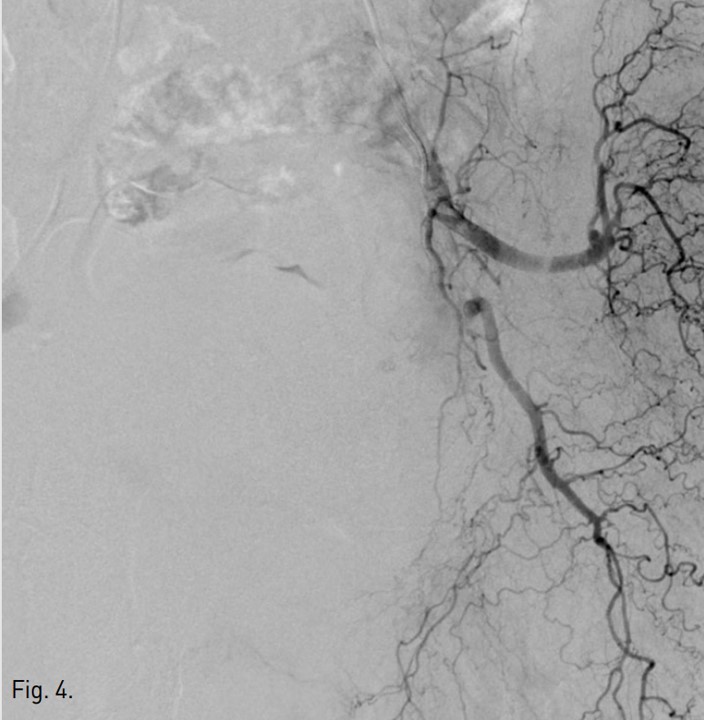

Fig. 1.

Fig. 1. The spot image shows the distended urinary bladder, filled with the diluted contrast media injected through a Foley catheter.

방광을 희석된 조영제로 채운 후 얻은 좌측 내장골동맥조영 사진에서 좌측 아래방광동맥(inferior vesical artery)이 두드러지게 커져 보임(Fig. 1, 2). 우측 내장골동맥조영 사진에서는 이상소견 보이지 않음.

우측 총대퇴동맥을 역방향천자하여 5F sheath(Terumo, Tokyo, Japan)를 삽입함. 5F Robert uterine catheter(Cook, Bloomington, USA)를 사용하여 좌측 내장골동맥을 선택한 후 방광에 삽입되어 있는 Foley catheter를 통해 10%로 희석된 조영제 100ml를 방광 내로 주입한 다음 동맥조영술을 시행함(Fig. 1, 2). 좌측 내장골동맥조영술에서 좌측 아래방광동맥이 두드러지게 커져 보여, 좌측 방광동맥을 미세도관(Progreat, Terumo, Tokyo, Japan)과 미세유도철사(GT wire, Terumo, Tokyo, Japan)로 superselection한 다음 gelfoam으로 색전하였음(Fig. 3). 색전술 시행 후 얻은 좌측 내장골동맥조영술에서 더 이상 방광동맥이 보이지 않았음(Fig. 4) 우측 내장골동맥조영술에서는 이상소견 보이지 않아 우측에서는 색전술을 시행하지 않음. 이후 환자는 혈뇨 증상이 호전됨.